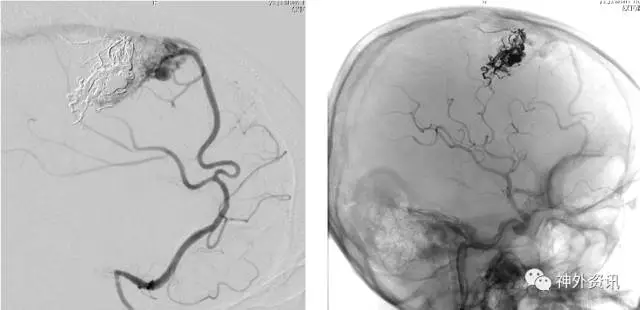

(左:Envoy DA导引导管-右侧椎动脉V3段;右:支架导管成功超选左侧大脑后动脉)

(支架辅助弹簧圈栓塞-动脉瘤不显影,载瘤动脉通畅)

(头颅CT:蛛网膜下腔出血,右侧额叶混杂高密度占位伴局部钙化)

(脑动脉CTA:前交通动脉瘤+右侧额叶AVM)

(右侧额叶AVM:双侧大脑前动脉+右侧大脑中动脉供血,静脉引流入矢状窦)

(左侧颈内动脉优势供血前交通微小动脉瘤2枚)

(治疗计划:支架辅助弹簧圈栓塞2枚前交通动脉瘤)